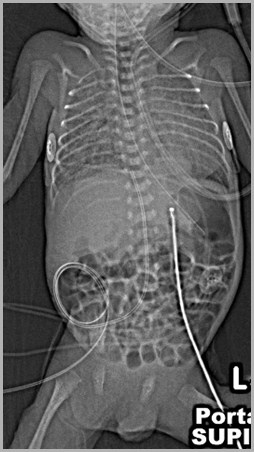

UAC and UVC Positions

Both should be above the diaphragm

UAC should be between T6 and T9

UVC should be in the IVC as it enters theright atrium (T8-T9)

Double lumen catheter is usually, but notalways, UVC

Two UACs, one in internal iliac, other in aorta

Auckland

Two UACs, one at T7, the other at L3UVC in portal vein

T7

L3